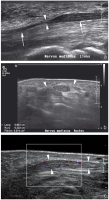

Abbildung 4: Sonographischer Querschnitt durch den Karpaltunnel einer Patientin mit klinischem Verdacht auf ein Karpaltunnelsyndrom. Der Nerv weist eine grenzwertige Querschnittsfläche von 0,11 cm2 auf, allerdings zeigt sich bei Hyperextension ein weit unter das Ligamentum carpi transversum (Pfeilspitzen) reichender Muskelbauch (M).* : normale Beugesehne.

Abbildung 6: Sonographischer Längsschnitt ("Extended field of view"-Sonogramm) durch den Nervus peronaeus bei einem Patienten nach Kniegelenksluxation mit Ausbildung eines "Neuroma in continuity". Der Nerv (Pfeilspitzen) ist bei erhaltener äußerer Hülle langstreckig aufgetrieben (Doppelpfeil) und von mehreren Traktionsneuromen (Pfeile) durchsetzt.

Abbildung 7: Sonographischer Längsschnitt durch den Nervus radialis (Pfeilspitzen) bei einem Patienten mit Radialisparese nach operativer Versorgung einer Humerusschaftfraktur. Der Nerv wird durch die vom Knochen etwas abstehende Platte (kurze Pfeile) abgedrängt und komprimiert (langer Pfeil).